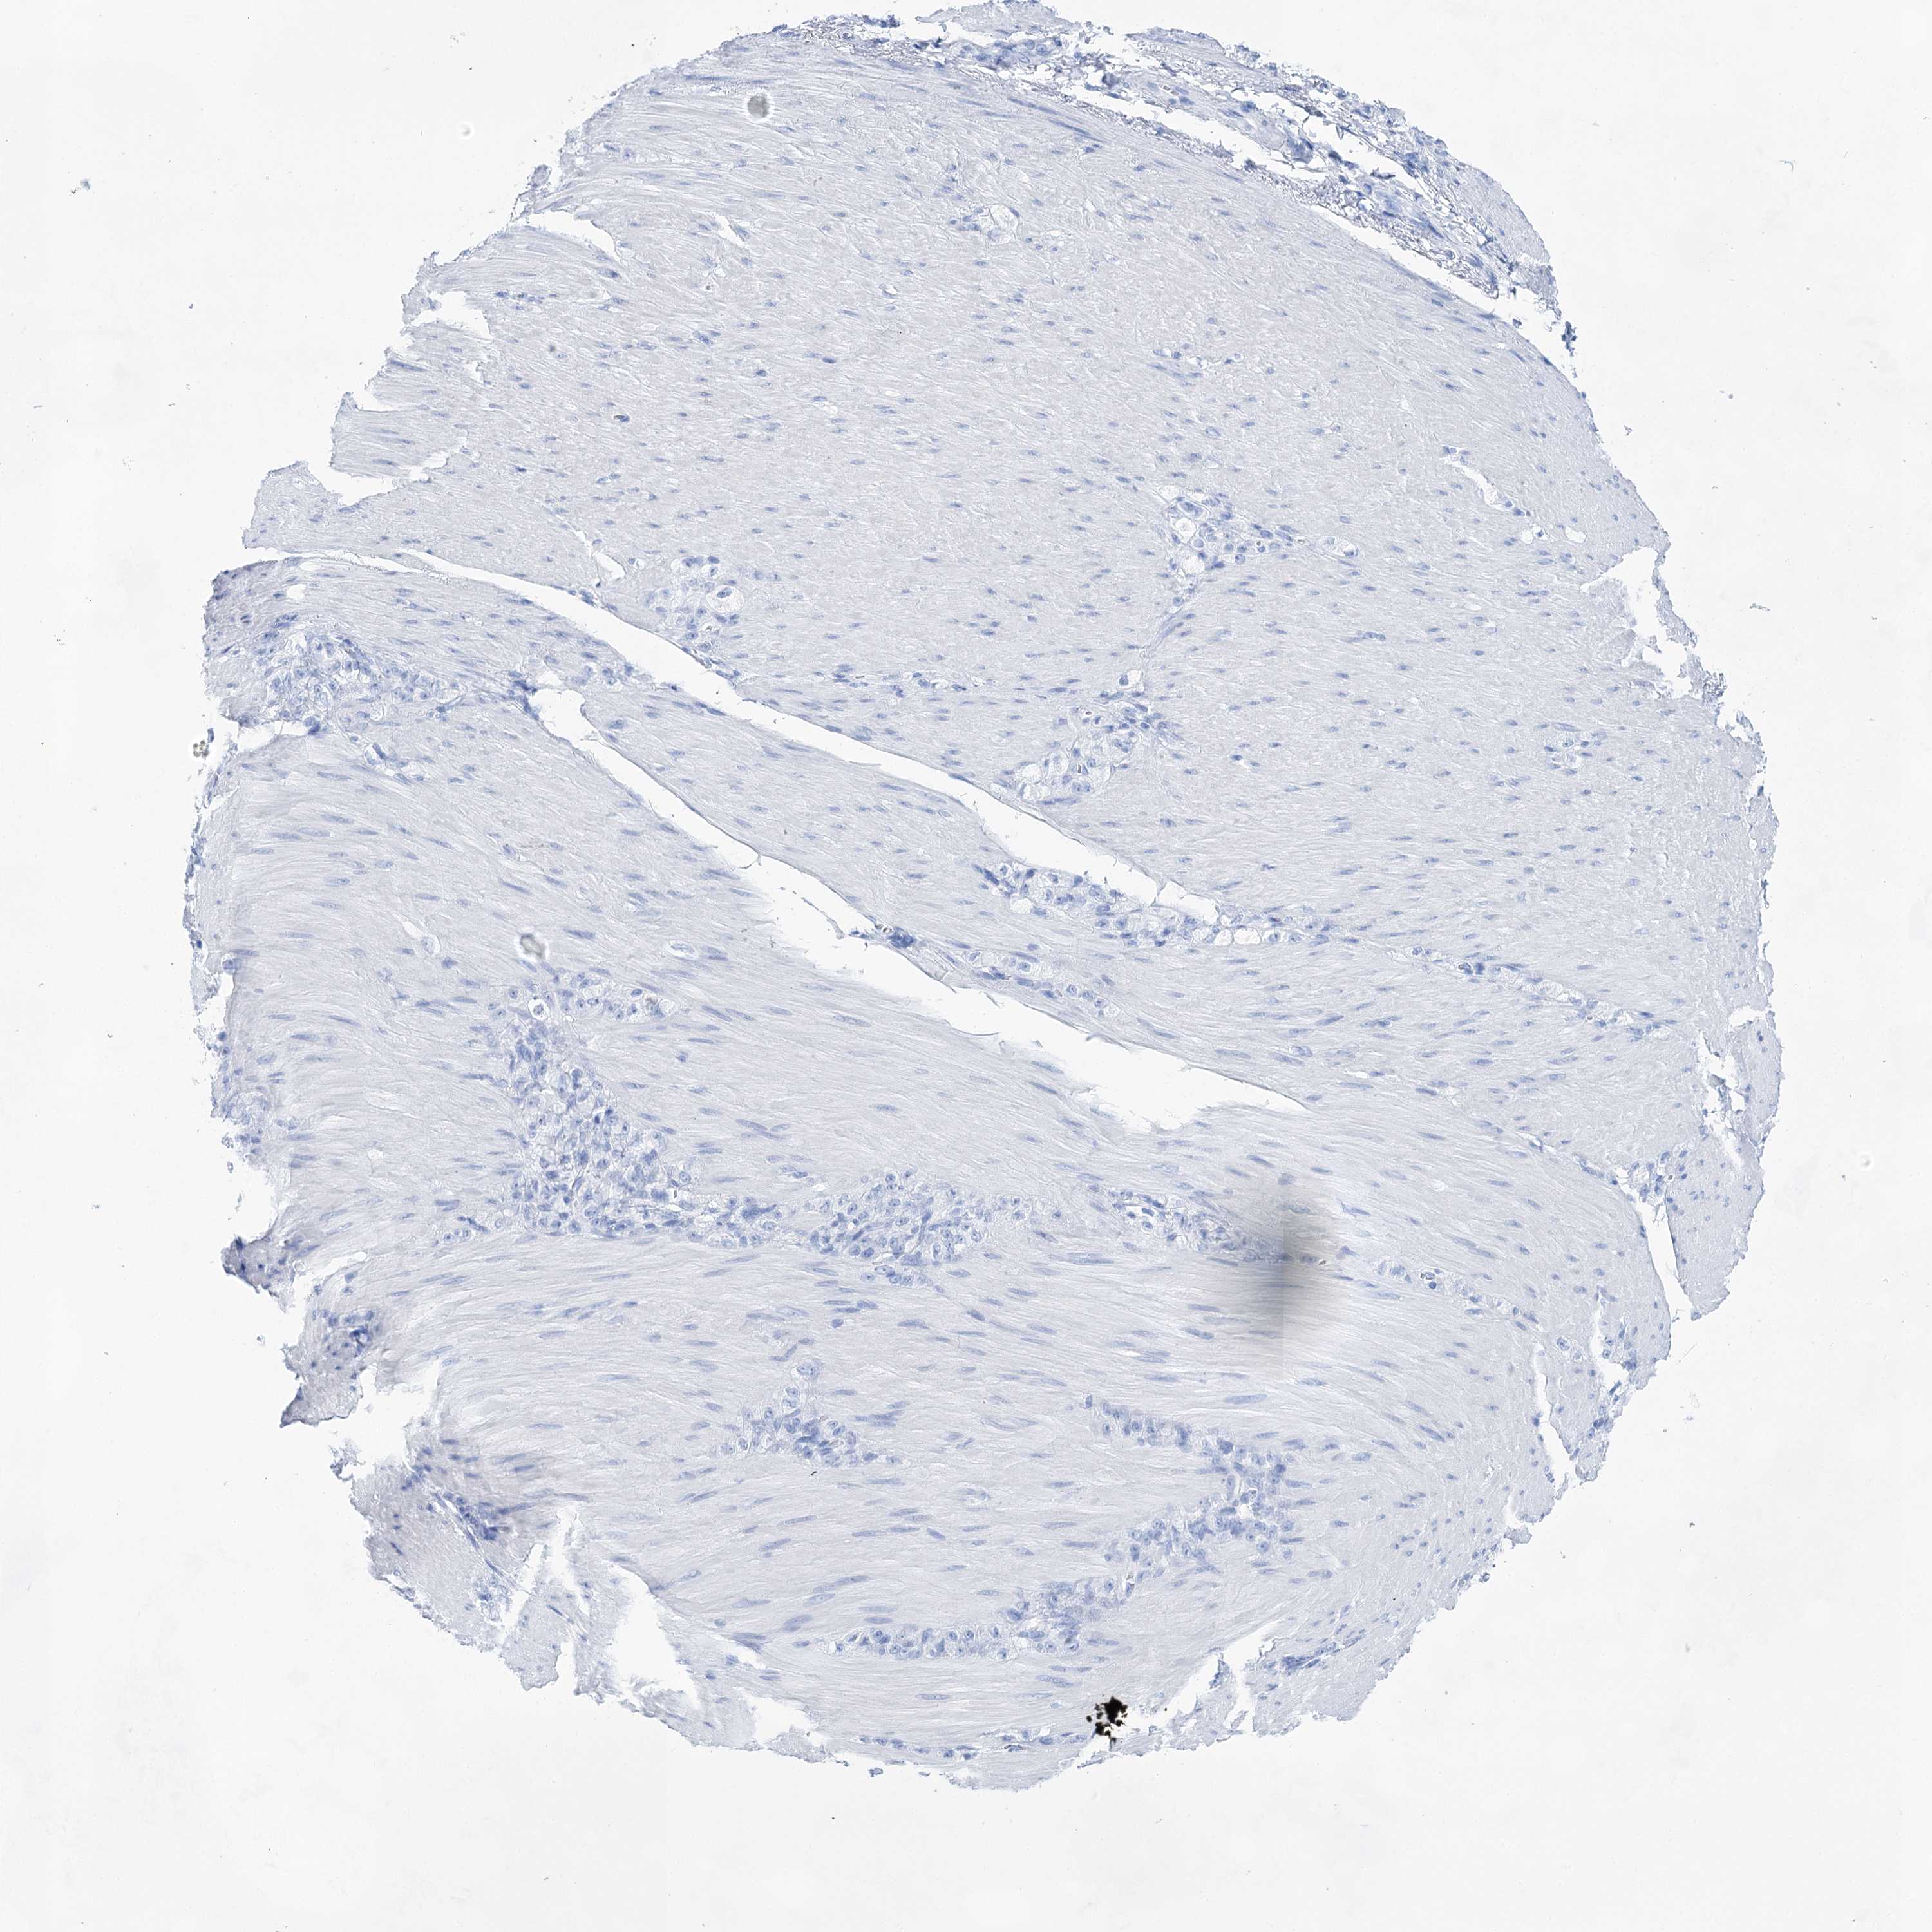

STOMACH CANCER - Protein expressioni

A mouse-over function shows sample information and annotation data. Click on an image to view it in a full screen mode. Samples can be filtered based on level of antibody staining by selecting one or several of the following categories: high, medium, low and not detected. The assay and annotation is described here.

Note that samples used for immunohistochemistry by the Human Protein Atlas do not correspond to samples in the TCGA dataset.

Antibody stainingi

Antibody staining in the annotated cell types in the current human tissue is reported as not detected, low, medium, or high, based on conventional immunohistochemistry profiling in selected tissues. This score is based on the combination of the staining intensity and fraction of stained cells.

Each image is clickable and will lead to virtual microscopy that enables deeper exploration of all samples and also displays staining intensity scores, fraction scores and subcellular localization as well as patient and tissue information for each sample.

Antibody HPA029855

Antibody HPA029856

Antibody CAB026343

Staining

High

Medium

Low

Not detected

Intensity

Strong

Moderate

Weak

Negative

Quantity

>75%

75%-25%

<25%

None

Location

Nuclear

Cytoplasmic/membranous

Cytoplasmic/membranous,nuclear

Adenocarcinoma, NOS